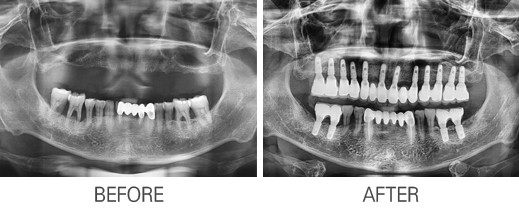

Ä«Å×°í¸®

: Àüü ÀÓÇöõÆ®

Àüü ÀÓÇöõÆ®